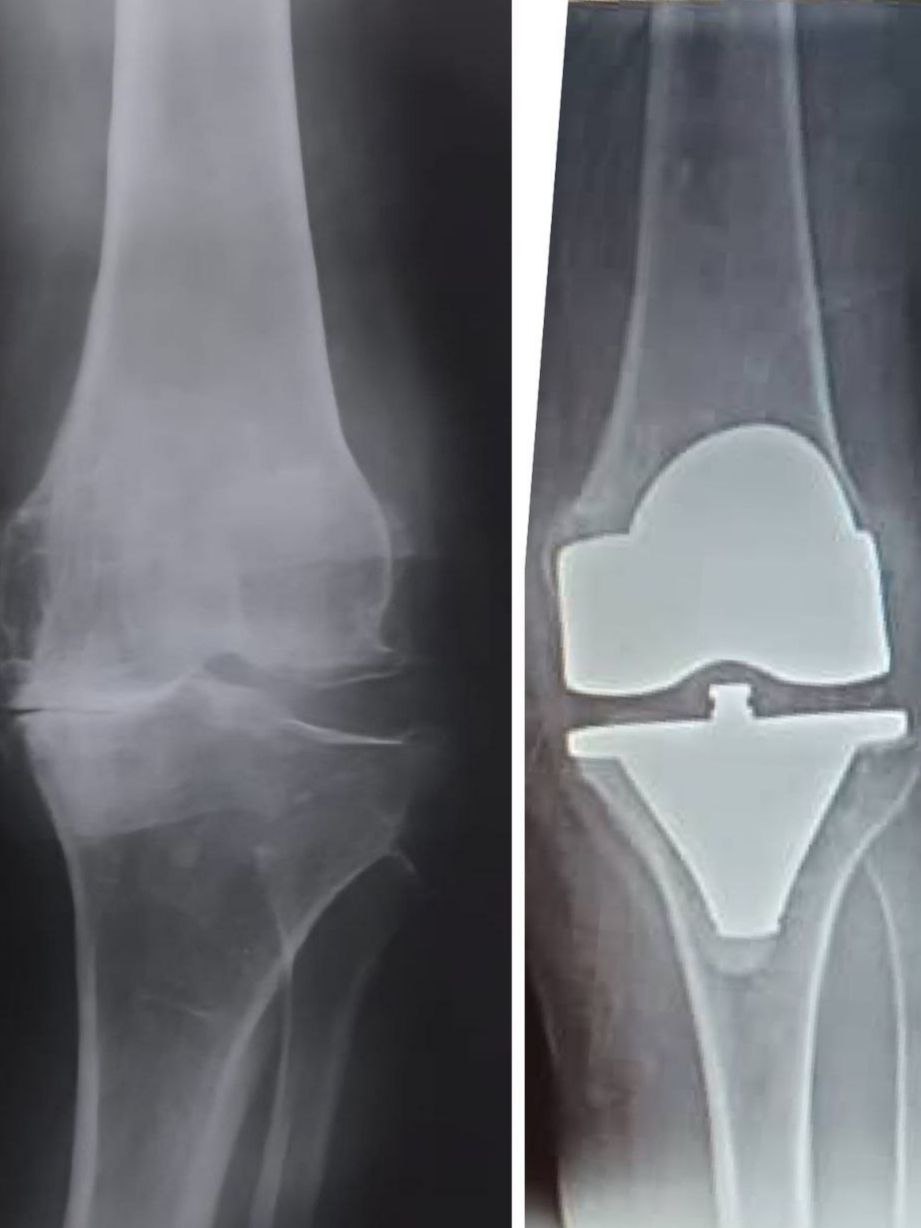

مفصل ركبة

تم استبدال المفصل المتآكل بمفصل صناعي عالي الدقة من شركتنا بالتعاون مع الدكتور [وليد العبد]. تُظهر الصورة تحسّن المحور واستعادة الحركة الطبيعية للمفصل بفضل دقة الزرع وأناقة التقنية المستخدمة، مما يعكس جودة منتجاتنا وكفاءة الفريق الجراحي